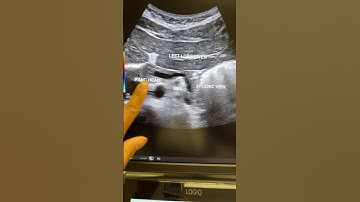

How to Scan the Pancreas